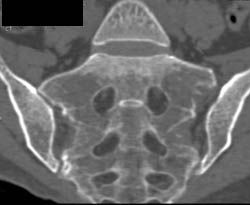

Metatarsal Fractures